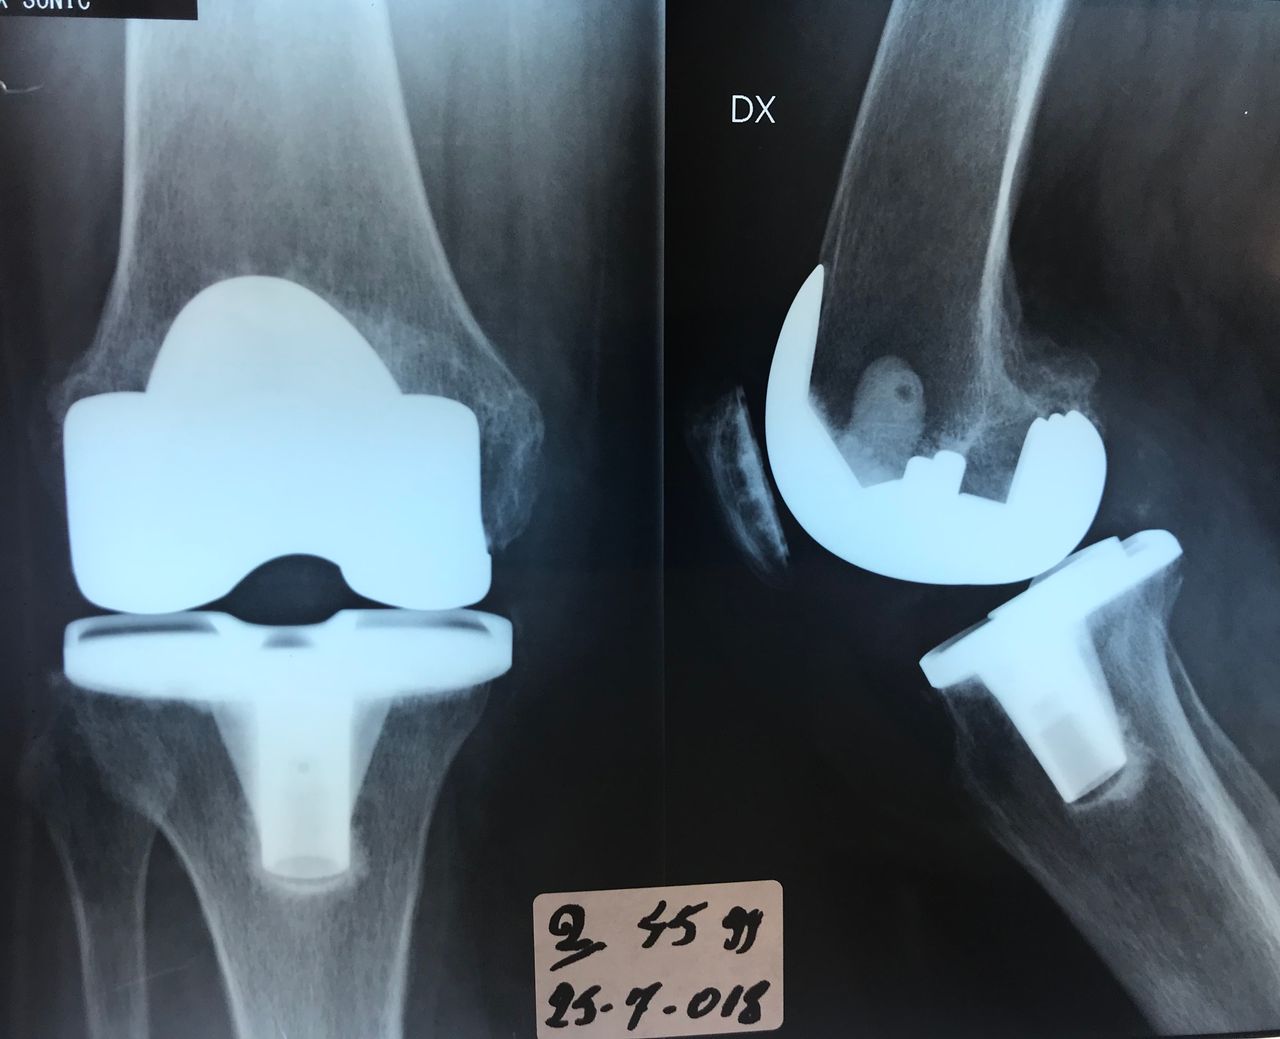

La protesi di ginocchio

• Ortopedia del ginocchio